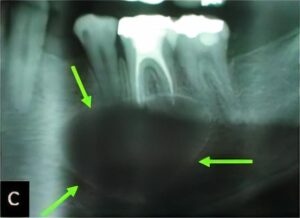

のう胞

のう胞は、何らかの理由で“水を含んだふくろ”ができてしまう病気です。特に顎骨は、のう胞ができやすいと言われています。

顎骨ののう胞では、虫歯から発生する「歯根嚢胞」が大半を占めていますが、くちびるにできる「粘液嚢胞(唾液が貯まった嚢胞)」や「含歯性嚢胞(埋伏歯にできる)」など様々な種類があります。

当科ではCT、MRI、病理組織診(良性悪性の確認検査)などの検査・診断、および治療(手術)を行っています。